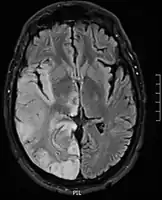

Hemispheric gyriform hyperintense signal variations -

Axial fluid-attenuated inversion recovery MRI image demonstrating tumor-related infiltration involving lenticular nuclei (Arrow). -

Axial fluid-attenuated inversion recovery MRI image demonstrating tumor-related infiltration involving both temporal lobes (Short arrow), and the substantia nigra (Long arrow).